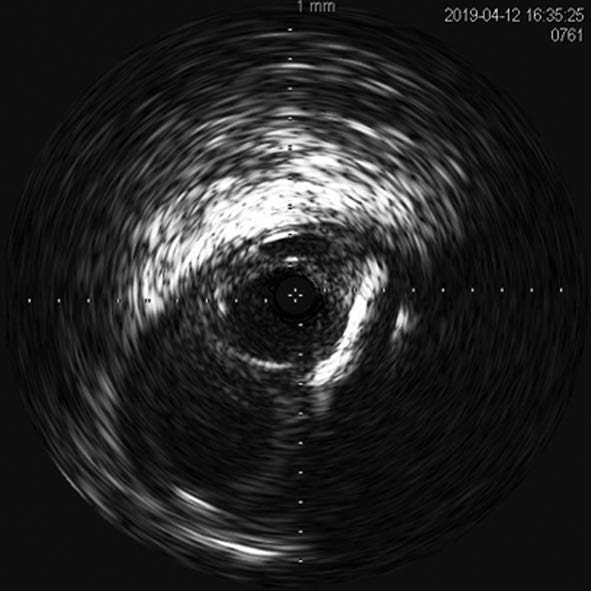

右大腿動脈穿刺、0.035 inchワイヤーを用いて、ガイディングシース 6 Fr 60 cmを左外腸骨動脈まで誘導し、造影を行った(図1.2)。体表面エコーガイドのもと、マイクロカテーテルと0.014 inch フロッピー300 cmワイヤーで、確実に浅大腿動脈入口部から血管真腔内を進めた。0.014 inch フロッピー300 cmワイヤーを抜去し、血管狭窄部貫通用カテーテルに交換し、閉塞部位を慎重に進め、貫通に成功した。血管狭窄部貫通用カテーテルにエクステンションワイヤーをつなげ、マイクロカテーテルを抜去、0.018 inchの径 2.0/長 20 mmバルーンで閉塞部位を拡張した。マイクロカテーテルを末梢まで進め、血管狭窄部貫通用カテーテルを抜去、0.014 inch 300 cm ワイヤーに交換、血管内超音波で病変部の観察を行った。ほぼ真腔を捉えていることが確認できたため、径 4.0/長 250 mmバルーンで閉塞全域を拡張した。一部石灰化病変により、拡張不良部位を認めたため(図3)、径 3.0/長 40 mm ノンコンプライアントバルーンで追加拡張を行った。再度、径 4.0/長 250 mmバルーンで閉塞全域を拡張した(図4)。血管内超音波で閉塞領域を観察し、ほぼ真腔を捉えていることが確認できた。ついで、径 5.0/長 250 mmバイアバーン® ステントグラフトを留置し、グラフト内をバルーンで後拡張した。血管内超音波でグラフト拡張および浅大腿動脈入口部を確認した(図5.6)。結果、左浅大腿動脈の良好な血流を得た(図7)。